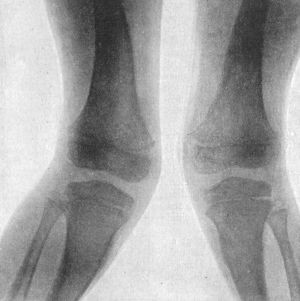

260 135.Genu Valgum and Genu Varum

265 136.Female Child with Right-sided Genu Valgum, the result of Rickets

266 137.Double Genu Valgum; and Rickety Deformities of Arms

267 138.Radiogram of Case of Double Genu Valgum in a Child

268 139.Genu Valgum in a Child. Patient standing